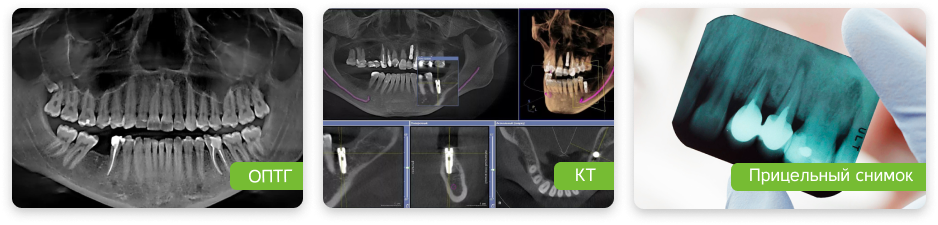

В стоматологической клинике Roott мы стараемся сохранить каждый зуб. Сначала делаем диагностику: осмотр, снимки, иногда - анализы, а уже потом ищем причину.